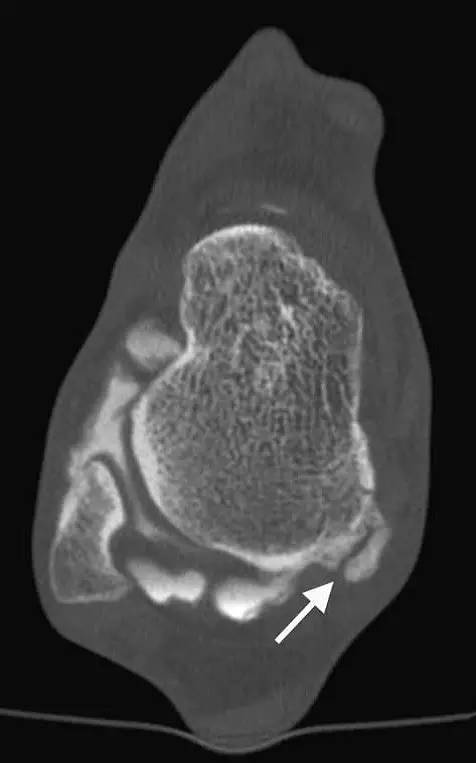

12. Cedell 骨折

距骨后内侧结节骨折。

Cedell 骨折的 CT 片 (来源:Fracture of the posterior medial tubercle of the talus :A case report and review of the literature. Acta Orthop. Belg., 2007, 73, 804-806)